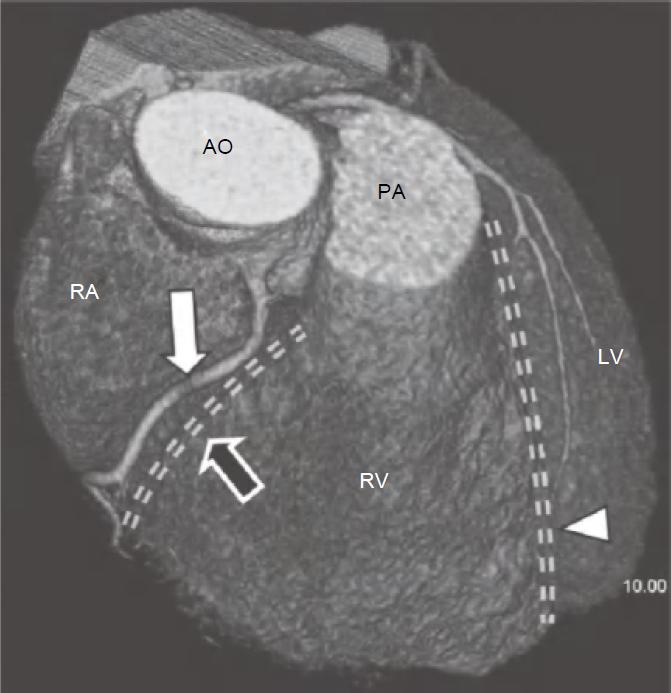

冠状动脉左主干(LMS)通常起源于左冠窦,位置低于RCA开口平面。通常在左心耳及肺动脉主干之间走行约1~2cm后分为LAD及左旋支(LCX),LAD在前室间沟内向下延伸至心尖(图13-1),LCX在左房室间沟(LAVG)内向后走行(图13-2)。

图13-1 左前降支(箭)起自左主干分叉处,并在前室间沟(虚线)内走行,为前壁、心尖部及大部分室间隔供血

AO.主动脉;PA.肺动脉;RV.右心室;LV.左心室